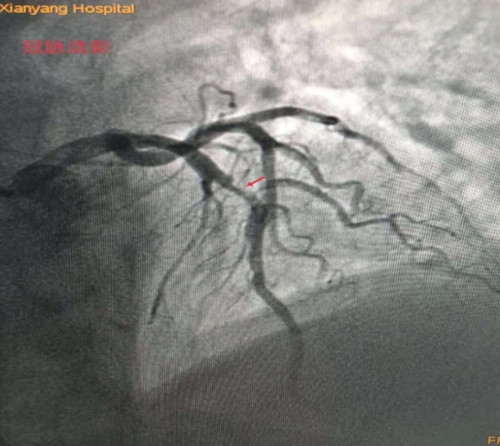

李新国主任为蒿大叔做了急诊冠脉造影检查,提示前降支近中段90%狭窄, D1开口99%狭窄,可见血栓影,结合术前心脏超声检查发现患者心脏腱索水平以下左室前间壁、前壁、前侧壁运动搏幅减低,梗死范围大,考虑罪犯血管为前降支近中段,在前降支近中段植入了一枚支架,开通闭塞血管。经过1个多小时的抢救,蒿大叔总算从鬼门关被救了回来了。